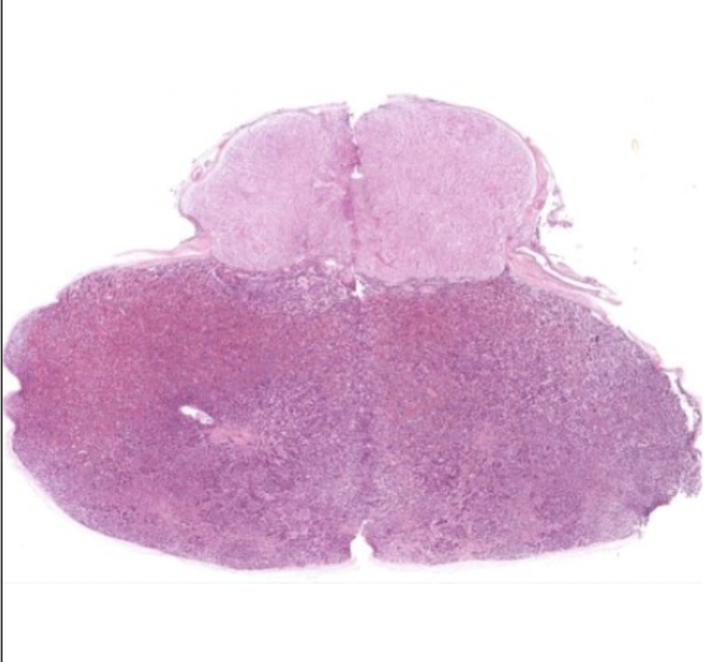

Thymus

Maturation and proliferation of lymphocytes

Surrounded by CT capsule

Several lobes separated by CT septa

Each lobe has dense cortex and inner paler medulla

Hassalls or thymic corpuscles

Flattened epithelial reticular cells in concentric layers